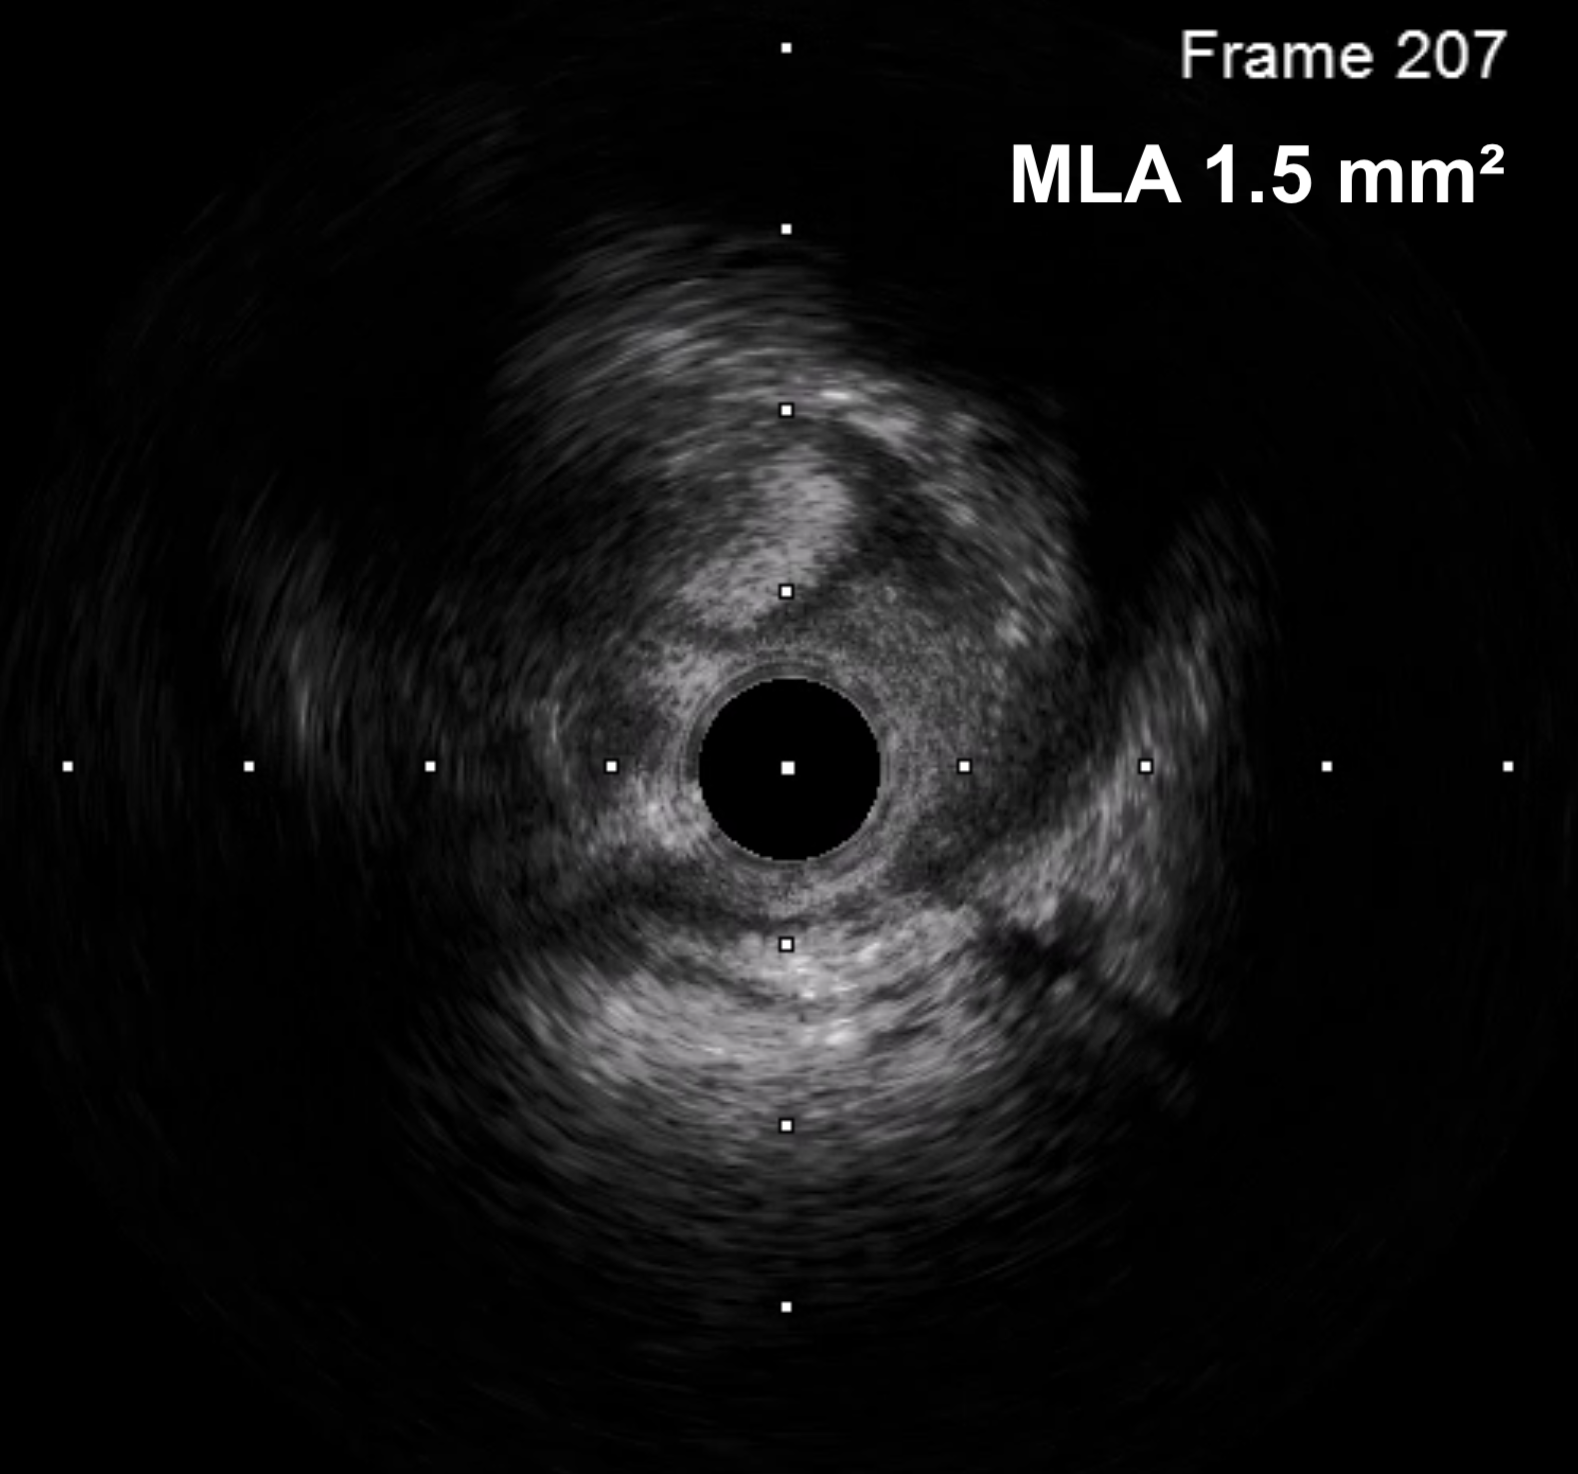

Patient had significant spasm of the bilateral radial arteries so right femoral artery access was obtained. A 6 Fr EBU 3.0 guide catheter was used to engage the left main coronary artery. A Sion wire was advanced into the LAD and a Sion Blue wire was advanced into the left circumflex. Pre-dilation was performed with a 2.5 x 12 mm semi-compliant balloon. IVUS showed MLA of 1.5 mm2 with intramural hematoma and evidence of plaque and thrombus. There was no evidence of SCAD on IVUS imaging. A 4 x 18 mm DES was placed in the left main and post-dilated with a 4.5 x 15 mm and 5 x 8 mm NC balloon. Final angiogram and IVUS confirmed excellent stent expansion/apposition with large MSA (11.8 mm2) and proximal stent edge in the ostium of the left main. Total air kerma was <500 mGy and and DAP was 50 Gy-cm2.